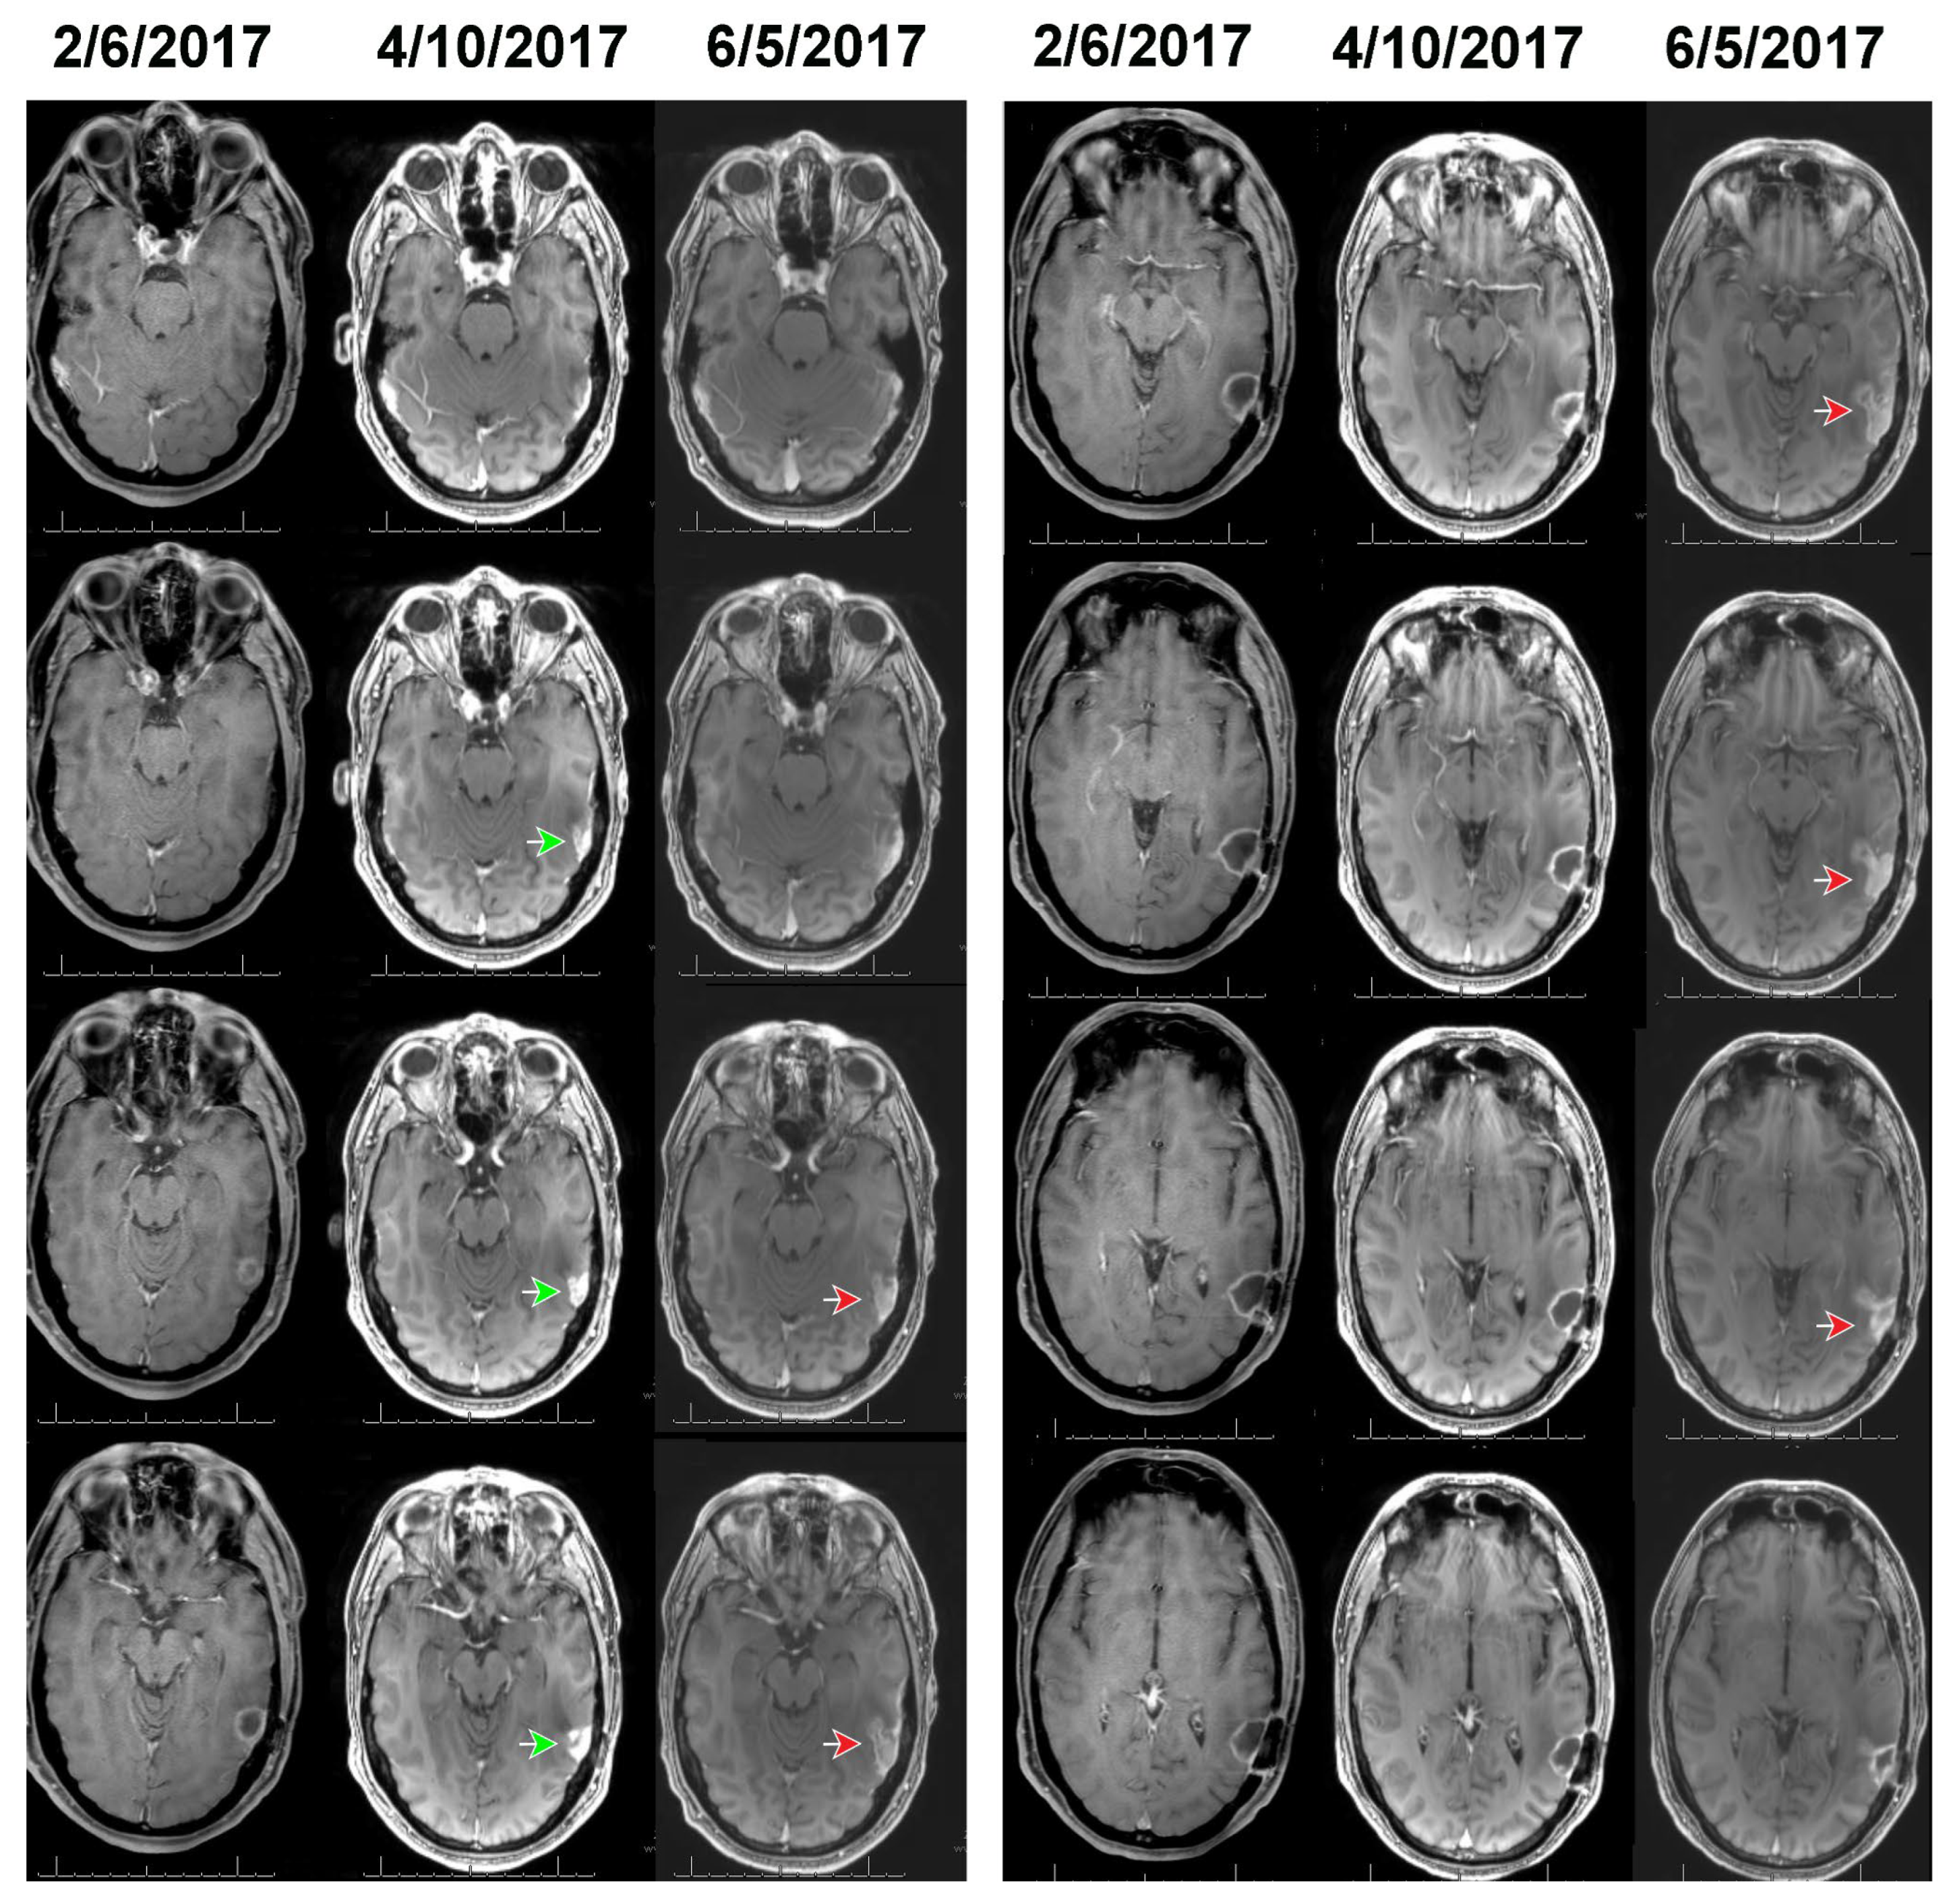

Figure 2 and Figure 3 show, respectively, the images of cases 1 and 2, before, at the time, and after detection of growth by volumetric analysis using the change-of-point method. The MRI of case 1 on 2/6/2017 reveals a surgical bed with linear enhancement along its margins (Figure 2). The MRI on 4/10/2017 reveals new nodular enhancement at the time of detection of tumor progression by volumetric analysis (Figure 2, green arrows). The neuro-oncologist diagnosed progression on 6/5/2017 (Figure 2 red arrows).

Figure 2. The T1c images of Case 1 (see Table 1 and Figure 1) shown before (2/6/2017) and at the time of detection of growth by our volumetric analysis (4/10/2017). The treating neuro-oncologist diagnosed tumor progression on 6/5/2017, as evidenced by informing the patient and family and initiating new clinical actions. Green and red arrows point to the tumor nodules on 4/10/2017 and 6/5/2017, respectively.